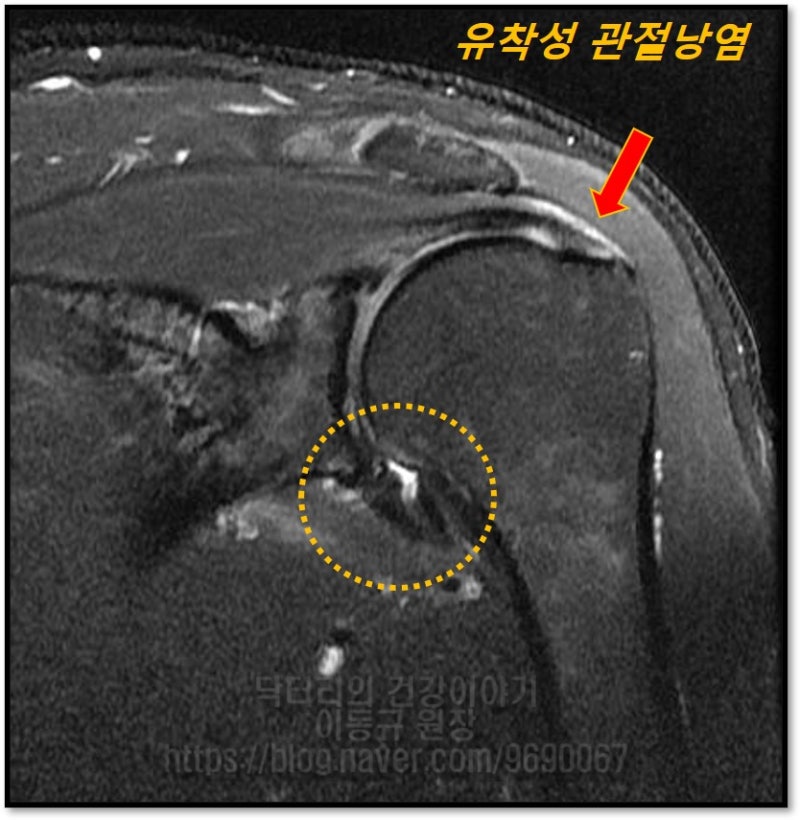

이 환자의 경우는 극상근의 부분 손상이 치유되지 않아 반복적으로 염증이 발생되었을 것으로 판단되며 이로 인한 유착성 관절낭염(오십견)이 치료되지 않았을 것으로 사료됩니다. 환자분께 극상근의 부분 손상과 유착성 관절낭염을 같이 치료 할 수 있는 뉴핌스 치료를 하였습니다.

또한 뉴핌스 치료 후에 추가적으로 손상된 극상근에 대해 프롤로 치료를 추가적으로 시행하였습니다.

뉴핌스 치료 직후에는 통증이 좋아졌다며 만족해 하셨으며 총 5주간의 치료를 시행하였으며 치료 후 환자는 일상생활에서나 운동시에도 지장이 없을 정도로 회복되었습니다.